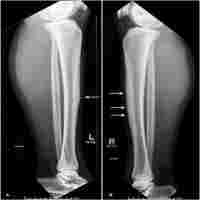

| Abstract | Background Leg pain in athletes is a common condition and is often related to tibial stress fracture. When non-operative treatment fails, the optimal surgical treatment is controversial. The aim of this study was to report a case of tension band plating of an anterior tibial stress fracture nonunion, treated previously with intramedullary nailing. To the best of our knowledge, this is the first reported case in which tension band plating was placed without removing the preexisting intramedullary nail. Case presentation The tibial shaft is a common location of stress fracture in athletes. Anterior tibial stress fractures are difficult to manage. When conservative treatment fails, intramedullary nailing is the mainstay of treatment. However, nonunion is a serious complication. In our case, a non-united anterior tibial stress fracture, treated with intramedullary nailing, was addressed with the application of a compression prebended plate over the nail in a 23-year-old French man of African origin who is an elite football player. At 3-months postoperatively he was pain free and started light exercises. At 6-months postoperatively, complete radiologic union of the fracture was evident. He was symptom free; he resumed at that time a full training program and he returned to play football at preinjury high competition level. Conclusions Compression plating is a valuable method of treating non-united anterior tibial stress fractures. We believe that anterior tension band plating is superior to intramedullary nailing in managing anterior tibial stress fractures, not only after failure of intramedullary nailing, but also as a first-line surgical treatment. This technique offers advantages, such as no violation of the extensor mechanism and risk of anterior knee pain, and directly addresses the underlying problem of distraction forces acting on the anterior tibial cortex and compromising fracture healing. Especially in high-level athletes, who cannot tolerate prolonged inactivity, early surgical intervention of anterior tibial stress fractures with tension band plating is a reliable option that can accelerate recovery. |